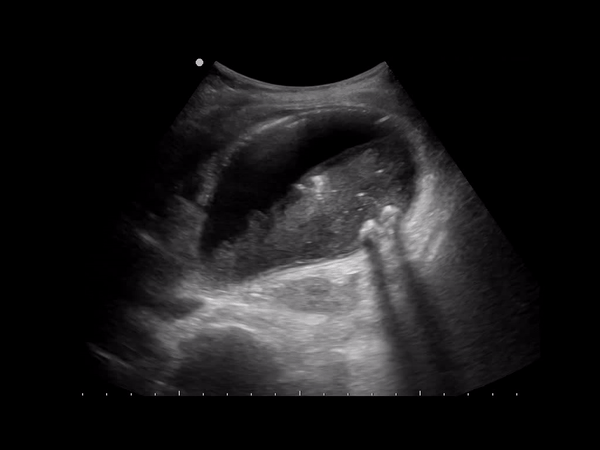

Sonographically you’re going to see echogenic mobile structures in the GB which can be solitary or numerous and vary in size from small to large. Stones will have posterior acoustic shadowing. The gallbladder can be completely filled with stones obscuring the lumen leading to the wall echo shadow WES sign.

Mobility of the stone can be observed by scanning the patients in left lateral decubitus as well as supine. Scan the intra and extra hepatic biliary tree to look for dilatation, stones or both.

Patients may be asymptomatic (up to 50%) or may have symptoms of biliary colic in the ruq or epigastrium. Other symptoms like pruritus, pale stools and intermittent jaundice may be present. On sonography will see biliary dilatation, depending on the location and size of the stones there may be GB enlargement and intrahepatic biliary dilatation as well. There will be echogenic stones with posterior acoustic shadowing. There may be one stone or multiple. At times the ductal stone may be distal to be observed with US, as such an Endoscopic Retrograde Cholangiopancreatography (ERCP) or Magnetic Resonance Cholangiopancreatography (MRCP) may be necessary for diagnosis.